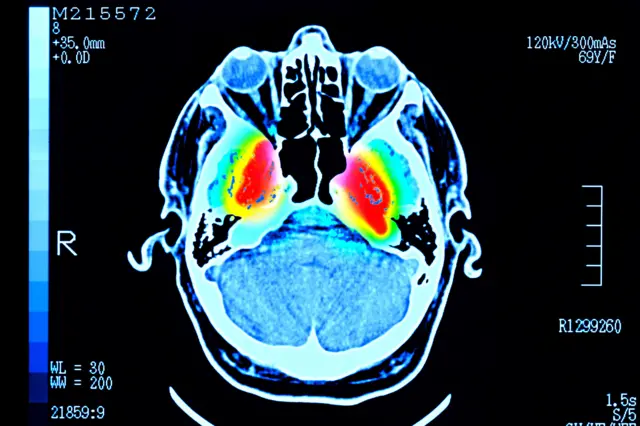

Cerca de 4.000 pessoas de até 90 anos fizeram exames que mostraram as conexões entre suas células cerebrais.

Esses padrões só agora aparecem devido ao volume de exames cerebrais reunidos no estudo, publicado na revista científica Nature Communications.